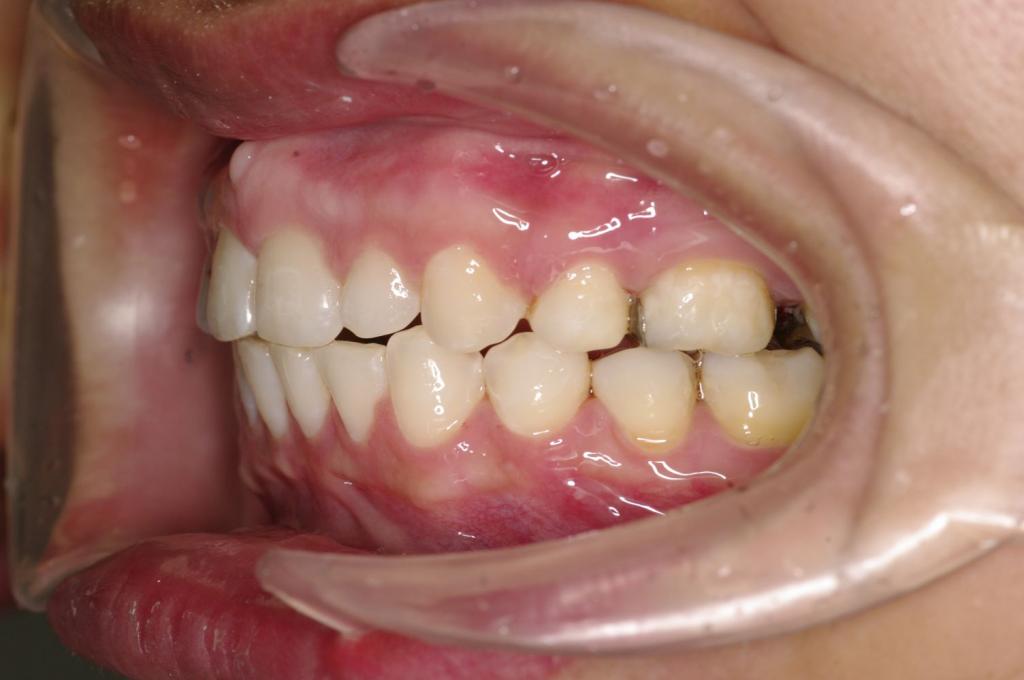

前歯、出っ歯・開咬の矯正治療

(治療期間、治療前後写真、治療方法、費用)WORKS